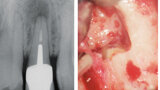

Aplikace MTA s použitím Produit Dentaires (PD) MAP System